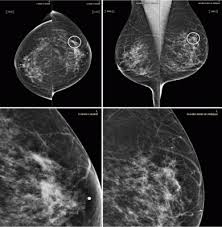

Can Ct Scan With Contrast Detect Breast Cancer - Breast Lumps Diagnosis Evaluation And Treatment : The cancer develops when abnormal cells crowd out healthy ones, potentially causing a lump in the breast or a bloody discharge from the nipples.. Breast cancer affects over 200,000 women each year. Luckily, i was still diagnosed pretty early. A ct scan is also called computerized axial tomography (cat) scan. In contrast with bone scans, which are only able to detect bone metastases, pet/ct has the advantage of concurrently imaging other common sites of breast cancer metastases such as the liver and lungs, says lead author patrick morris, a breast cancer specialist at memorial sloan kettering. This is an excellent way to take a needle biopsy for inflammatory breast cancer because imaging can show the best place to take the biopsy.

Learn the stage of your cancer. The term tomography comes from the greek words tomos (a cut, a slice, or a section) and graphein (to write or record). In contrast with bone scans, which are only able to detect bone metastases, pet/ct has the advantage of concurrently imaging other common sites of breast cancer metastases such as the liver and lungs, says lead author patrick morris, a breast cancer specialist at memorial sloan kettering. This is an excellent way to take a needle biopsy for inflammatory breast cancer because imaging can show the best place to take the biopsy. Ct scans are most often done as an outpatient procedure.

This test is most often used to look at the chest and/or belly (abdomen) to see if breast cancer has spread to other organs. Not necessarily is the whole body going to be scanned at that time. Once a nodule is found, a workup is done to see if it is cancer. If i had contrast on the earlier ct, my cancer would have been found 2 1/2 years earlier. Help check how well treatment is working and/or.

Ct scans can help doctors: If you have a large breast cancer, your doctor may order a ct scan to assess whether or not the cancer has moved into the chest wall. This substance is often called a tracer, because it helps reveal cancer in the body. The scan lets them:learn the cancer's stage. Computed tomography scan, ct scan, cat scan, and spiral or helical ct. 234 views answered >2 years ago Before the scan, you will either drink a liquid dye or be given an injection of dye into a vein in your arm. Breast cancer affects over 200,000 women each year. A pelvic ct scan can be used to detect several types of cancer. Contrast medium is a dye that helps body tissues show up more clearly on the scan. In contrast with bone scans, which are only able to detect bone metastases, pet/ct has the advantage of concurrently imaging other common sites of breast cancer metastases such as the liver and lungs, says lead author patrick morris, a breast cancer specialist at memorial sloan kettering. You are encouraged to drink clear liquids. This helps determine whether or not the cancer can be removed with mastectomy.

In general breast cancer can be detected on a routine chest ct scan regardless of if contrast media is used or not. Several types of cancer can form in the breast, making it the second most common cancer that affects american women. These scans expose you to more. Before a pet/ct scan, an iv that injects a small amount of a radioactive substance will be placed into one of your veins. Long story short i have a ct scan with contrast on 1st june to look for cancer in the abdominal cavity.